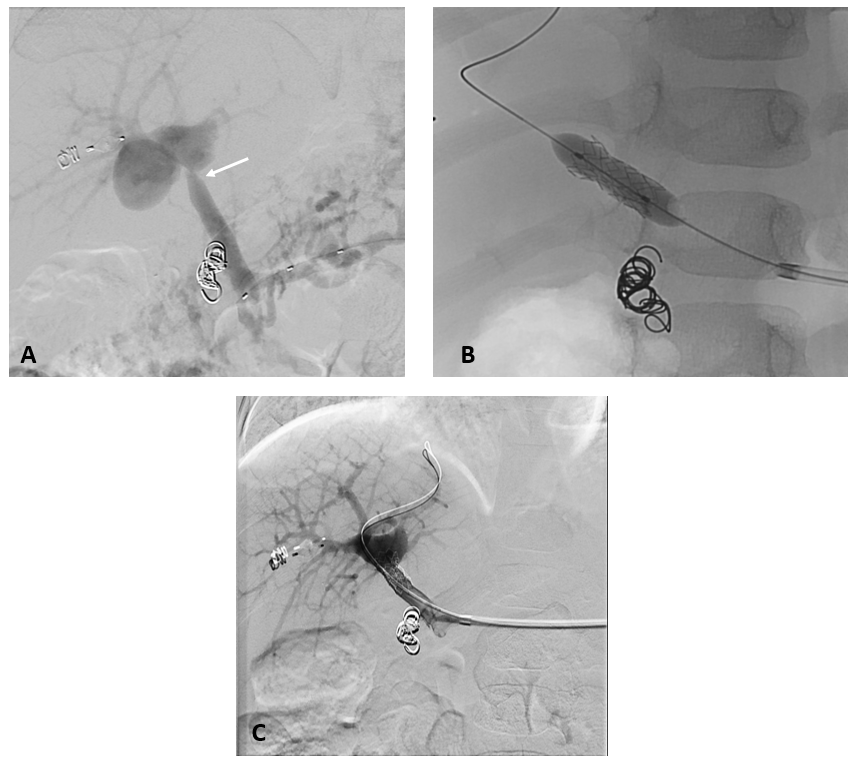

3- jähriger Junge mit stattgehabter Pfortaderthrombose (Verschluss der Pfortader).

Zustand nach Anlage eines Meso-Rex Shunts. Aktuell Größenzunahme der Milz und zunehmende Zeichen des Pfortaderhochdrucks. Sonographisch wurde dann der Verdacht auf eine Stenose (Verengung) der Shunts gestellt. In der Angiographie mit einem Zugang über Milz zeigte sich die vermutete Stenose (Pfeil in Bild A). Es wurde dann ein Stent eingebracht und mittels Ballon dilatiert (B). In der Kontrolle zeigte sich ein gutes Ergebnis mit Beseitigung der Engstelle. Dem Patienten ging es rasch besser.